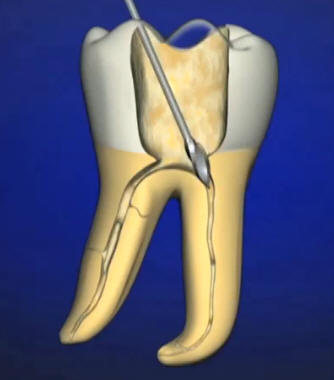

El ensanchador Gates Glidden tiene un extremo cortante corto, en forma de llama, con hojas cortantes laterales levemente espiraladas con ángulo muy inclinado respecto de la vertical. Generalmente tiene una pequeña guía no cortante en su extremo para minimizar su potencial de perforación de la superficie radicular.  Ver imagen izquierda

La cabeza cortante está conectada al vástago por un fino y largo cuello. Está numerado del 1 al 6 mediante marcas en el tallo del instrumento. Se utilizan para la ampliación y conformación de los conductos después del limado seriado y ensanchamiento con limas, en sus tercios cervical y a veces hasta el tercio medio. Ver imagen derecha

Los taladros Gates Glidden están diseñados con un punto débil en la parte del eje más cercana a la pieza de mano, de forma tal que el instrumento fracturado pueda ser retirado fácilmente del conducto.

Se fabrican de acero inoxidable y con un largo desde la punta hasta el contrángulo de 18 mm.